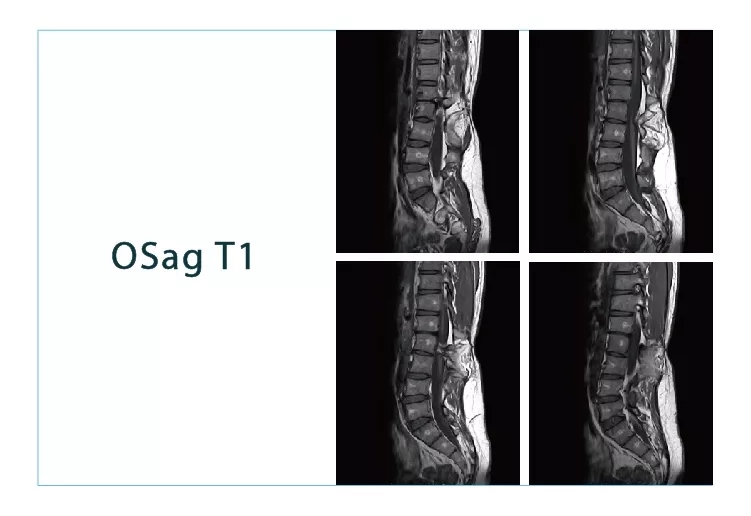

【朗润影像档案】磁共振影像病例分享(编号20180907)